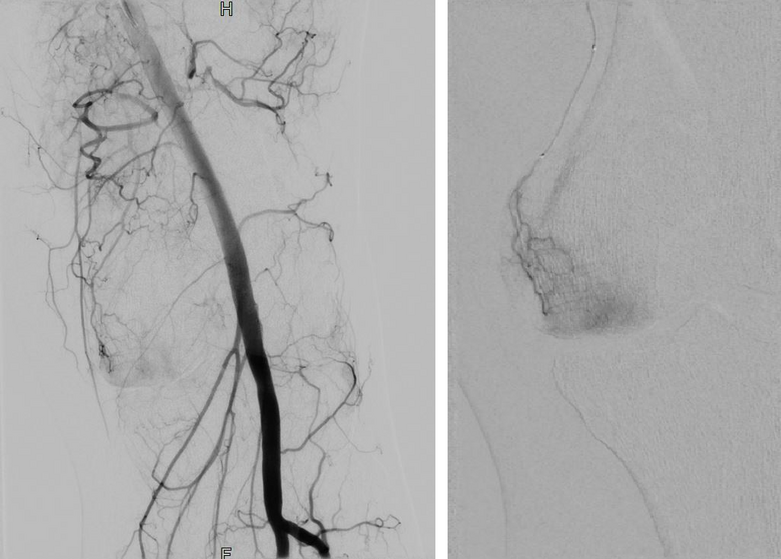

In der Radiologie erfolgt eine örtliche Betäubung der Leiste nach ausgiebiger Hautdesinfektion in Rückenlage auf dem Untersuchungstisch. Anschließend wird die Leistenschlagader punktiert und schmerzfrei mit dünnen Kathetermaterialien die entsprechenden feinen Zielgefäße unter Röntgenkontrolle im betroffenen Gelenk aufgesucht. Diese werden dann mit Imipenem/Cilastatin und gegebenenfalls zusätzlich mit Partikeln verschlossen (embolisiert), um so die Blutzufuhr zu den entzündeten Arealen zu unterbrechen. Je nach Anzahl der zu verschließenden Zielgefäße dauert der Eingriff in der Regel zwischen 45 und 90 Minuten. Am Ende des Eingriffs werden die Kathetermaterialien wieder vollständig entfernt, die Punktionsstelle in der Leiste abgedrückt und ein Druckverband angelegt.